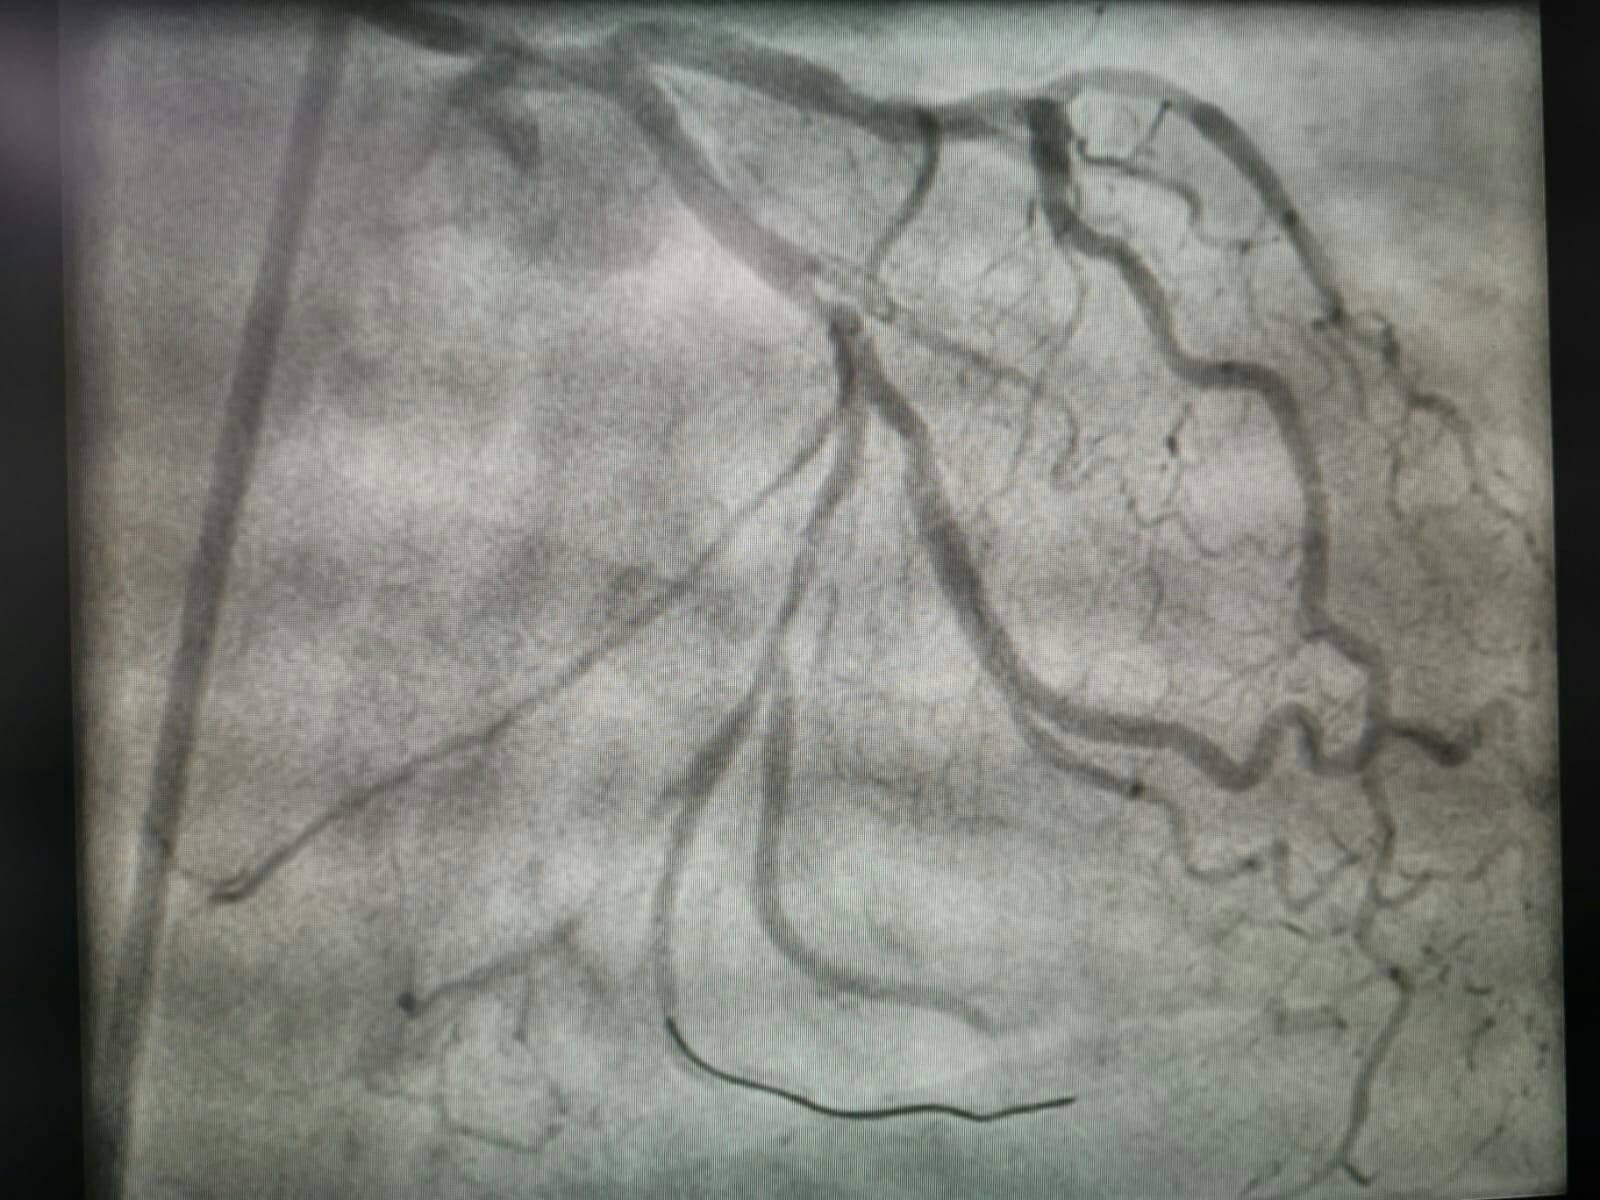

În data de 27.02.2019, la Spitalul Judeţean de Urgenţă Buzău a avut loc prima intervenţie efectuată pe angiograful spitalului – coronarografie diagnostică la un pacient în vârstă de 63 de ani, din municipiul Buzău, pacient diagnosticat cu factori de risc cardiovascular (diabet de tip II, HTA, dislipidemie), cu boală cardiacă ischemică (modificări EKG) şi angină pectorală instabilă. S-a efectuat angioplastie coronariană percutană, cu implantarea a două stenturi farmacologic active. După intervenţie, pacientul a fost transportat în Unitatea de Terapie Intensivă Coronariană a secţiei de Cardiologie, unde a fost monitorizat până la externare.

În zilele de 05 şi 06.03.2019, alţi patru pacienţi, cu vârste cuprinse între 55 și 75 de ani, din județul Buzău, au fost internaţi în spital, în Secţia Cardiologie, cu sindrom coronarian acut (infarct miocardic fără supradenivelare de segment ST, angină instabilă) şi au fost supuşi unor intervenţii coronariene.